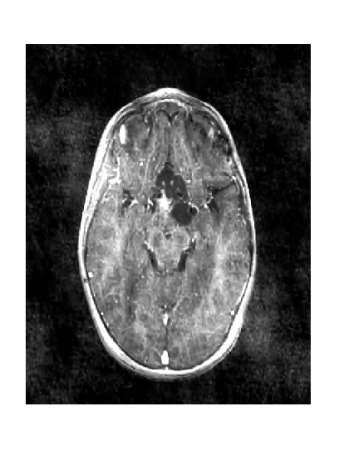

The effect of the scale difference would be most pronounced in the argument of Term 2, but also impacts and , since the values of these weighting terms also depend on . As shown in Figures 13 and 14, the intensity shift causes significantly reduced RSNR. We have designed an algorithm and a modification of reference based MRI to compensate for the shift in grayscale intensity and ensure high RSNR.

Figure 12 shows the effect of a 2-fold scale difference on LACS-MRI image reconstructions. There are extensive streaking artifacts and significant detail is lost compared to the ground truth and the reconstruction using the modified method. Clearly, the Grayscale Compensation for Reference Based MRI Algorithm (GSC) can reduce these artifacts and help improve the visibility of structure.